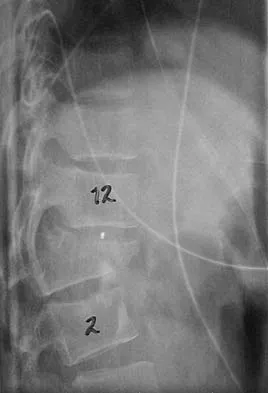

Question 37

A 7-year-old girl has had a painful forearm for the past 2 months. Examination reveals fullness on the volar aspect of the forearm. Radiographs and an MRI scan are shown in Figures 42a through 42c. Biopsy specimens are shown in Figures 42d and 42e. What is the most likely diagnosis?

Explanation